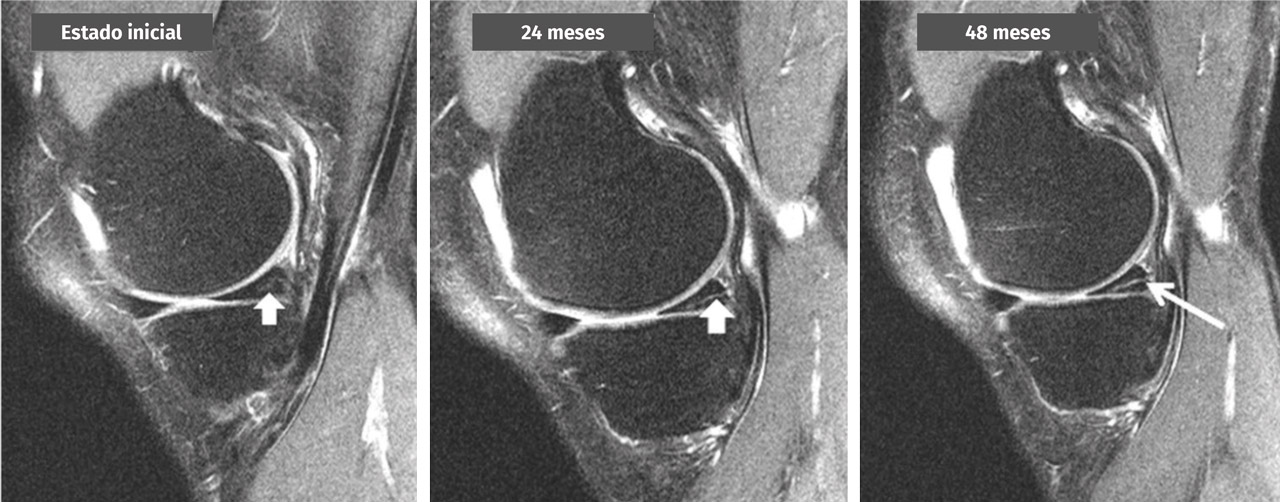

Una lesión degenerativa del menisco es una lesión de desarrollo lento en una persona de mediana edad o edad avanzada, que habitualmente consiste en una rotura horizontal del menisco. Estas lesiones son frecuentes en la población general y, a menudo, se detectan por casualidad en RM de la rodilla (Figura 2). Su etiología aún no ha sido bien definida. En muchos casos no hay antecedentes claros de una lesión aguda en la rodilla (grado B).

Figura 2. Transformación de una señal intrameniscal en una lesión horizontal en el cuerno posterior del menisco interno a lo largo de 4 años observada en una secuencia de resonancia magnética de rodilla de 3 teslas (cortesía de M. Englund).

¿Qué hallazgos sugieren la presencia de una lesión degenerativa del menisco en una resonancia magnética?

En RM, la lesión degenerativa del menisco normalmente se caracteriza por una señal intrameniscal que incluye un componente horizontal, que a menudo exhibe una comunicación con la superficie inferior del menisco en al menos 2 cortes de la RM. No obstante, también pueden darse patrones de rotura más complejos con múltiples configuraciones. La localización más habitual de una lesión degenerativa del menisco es el cuerpo y/o el cuerno posterior del menisco interno (grado B).